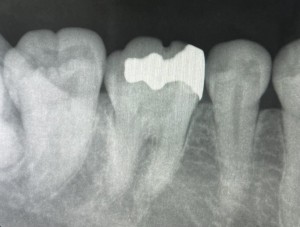

銀歯の隣の歯も黒く、虫歯になっていたため、エックス線写真を撮影しました。

治療前の歯は以下のような状態でした。